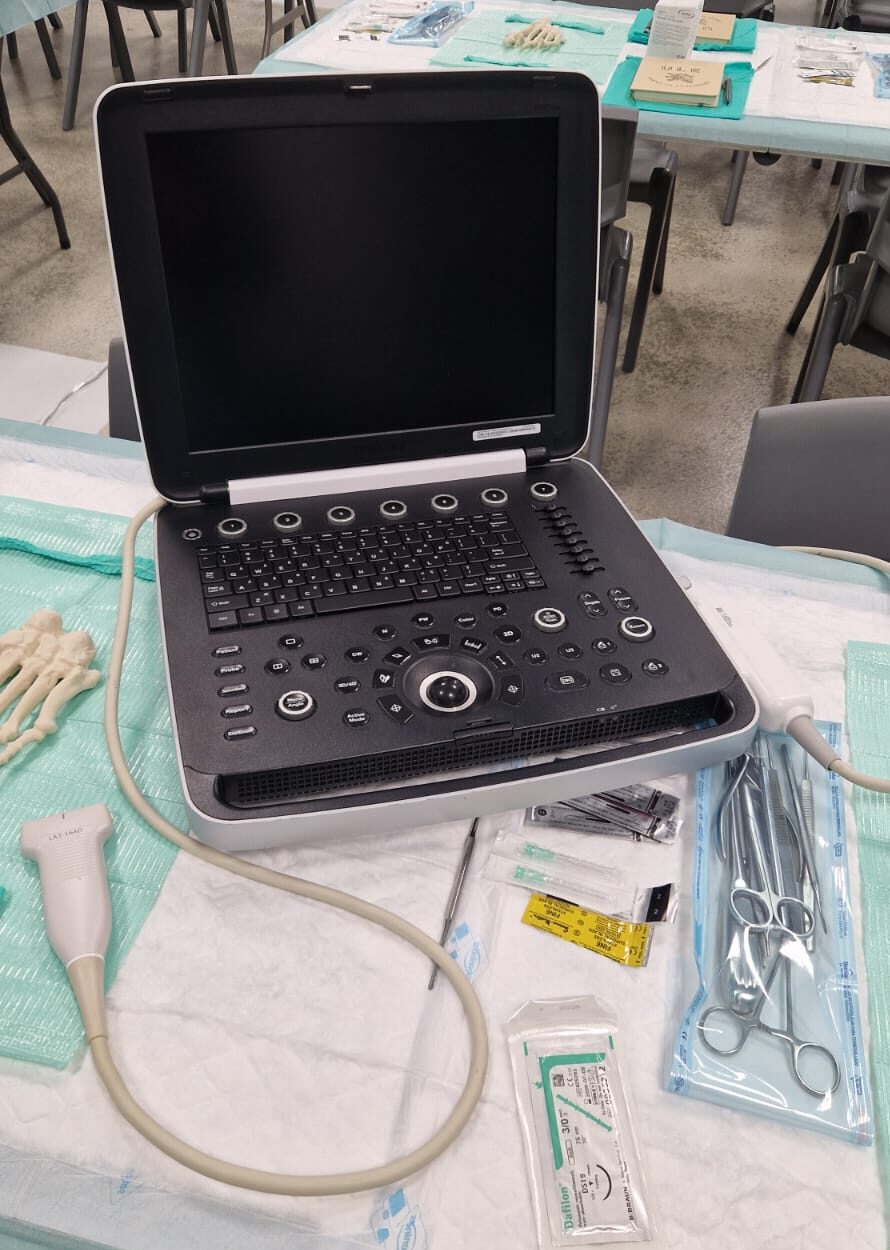

Samsung HM70A Plus

Sistema de ecografia portátil con muy buena calidad de imagen para su gama de precios con una mayor resolución y penetración en el diagnóstico.

Samsung HM70A Plus

- El ecógrafo Samsung HM70 EVO es un dispositivo portátil de alto desempeño, diseñado para cubrir una amplia variedad de aplicaciones clínicas y adaptarse a distintos tipos de pacientes. Cuenta con un flujo de trabajo eficiente, gran resistencia y una calidad de imagen de alta definición, lo que permite su uso en múltiples entornos y escenarios clínicos.

- 2 sondas a elegir

- Sonda Lineal LA3-16AD y Stick LS6-15.